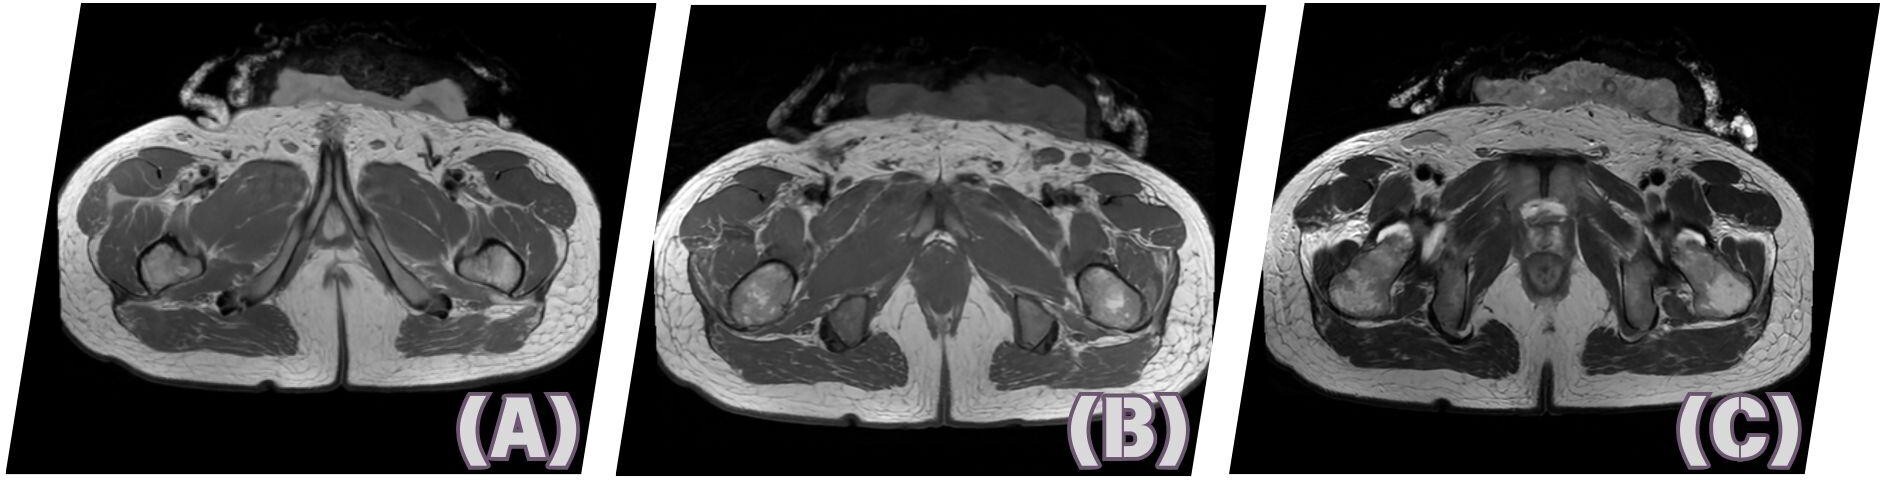

Diagnostics done included CBC which showed leukocytosis (WBC 16.8), increased neutrophils (82%), and thrombocytosis (Plt 458). Abdominopelvic CT scan showed an enhancing fungating soft tissue mass measuring about 7.3 x 12.6 x 9.6 cm (AP x W x CC) seen in the skin of the mid anterior lower abdominal region extending inferiorly to the left inguinal area with associated underlying minimal subcutaneous fat stranding. While MRI showed a lobulated fungating enhancing cutaneous mass corresponding to the CT findings.

_axial_on_pd_phase_(b)_axial_on_t1_phase_(.jpeg)